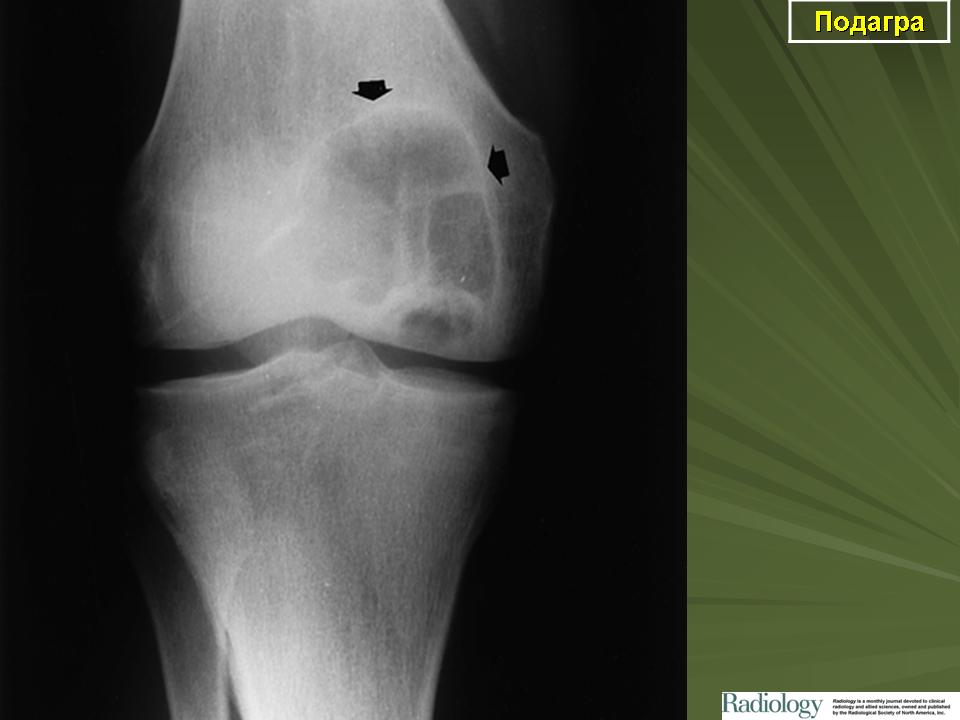

Рентгенологические проявления при подагре впервые описаны G. Huber в 1896 г. Позднее было проведено множество исследований, которые показали, что на ранней стадии болезни не существует каких-либо характерных изменений. Затем на рентгенограммах появляются признаки деструкции костей и хряща, обусловленные отложением кристаллов урата натрия в субхондральной кости.

Существует несколько классификаций рентгенологических изменений при подагре. Так, Е. Кавеноки-Минц выделяет три стадии хронического подагрического артрита (1987):

• I - крупные кисты в субхондральной кости и в более глубоких слоях. Иногда уплотнение мягких тканей;

• II - крупные кисты вблизи сустава и мелкие эрозии на суставных поверхностях, постоянное уплотнение околосуставных мягких тканей, иногда с кальцификатами;

• III - большие эрозии, но менее чем на 1/3 суставной поверхности, остеолиз эпифиза, значительное уплотнение мягких тканей с отложением извести.

Более поздней является классификация, предложенная М. Cohen, В. Emmerson (1994), согласно которой к основным рентгенологическим признакам при подагре относят следующие:

• в мягких тканях - уплотнения;

• эксцентрическая затемненность, обусловленная тофусами;

• кости (суставы) - суставная поверхность отчетливо представлена;

• юкстаартикулярный остеопороз отсутствует;

• эрозии (пробойник, краевой склероз).